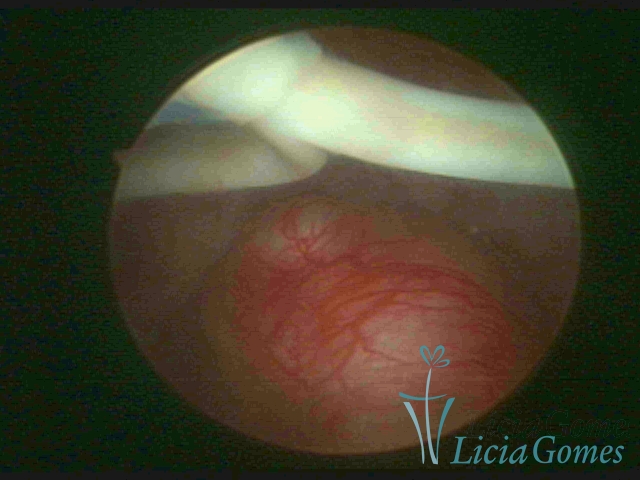

Cavidade uterina com DIU